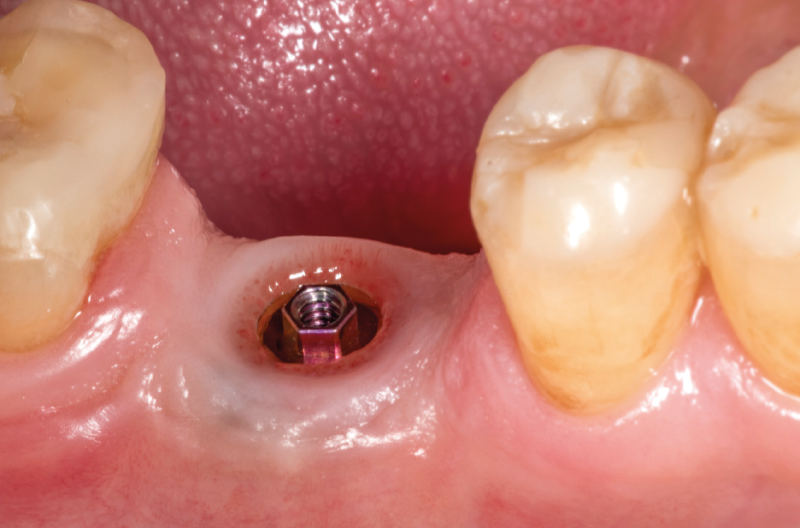

View of clinical situation three months after implant placement: soft tissues are healed around the healing screw